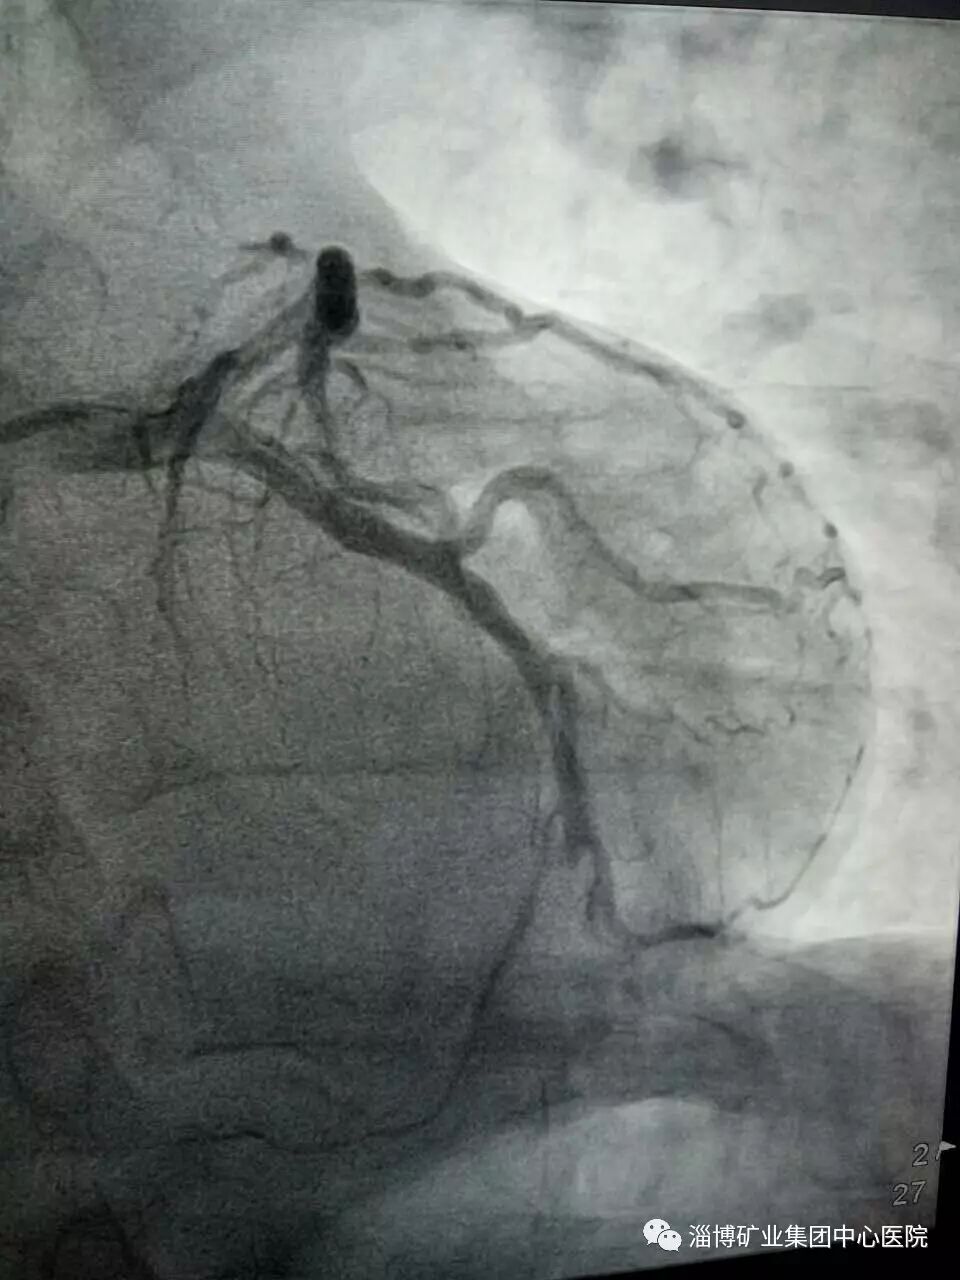

李老奶奶于7月20日下午4时突然感到颈部有紧缩感,便立即卧床休息,但症状不仅没有改善,反而加重,家人立即呼叫120,在120救护车上,淄矿医院接诊人员紧急为李老奶奶做了心电图,提示急性前壁心肌梗死,并当即给予急性心梗急救标准药物对症治疗,以及简要沟通介入手术治疗方法。同时电话通知该院胸痛中心值班人员,实现一键启动胸痛中心绿色通道。

当救护车到医院后,胸痛中心的孙大夫和护士已经在等候李老奶奶了,平稳移到病床上采血后,就直接进入了导管介入室,全程有大夫和护士陪伴,那流程那效率真是让李老奶奶家人感动啊!

血样检查结果没什么问题,介入团队当即开始手术,消毒、穿刺、造影、支架植入……娴熟的操作流程一气呵成,15分钟后,李老奶奶的心脏冠状动脉血管就恢复了血流通畅,颈部的紧缩感自然就消失的无影无踪了。